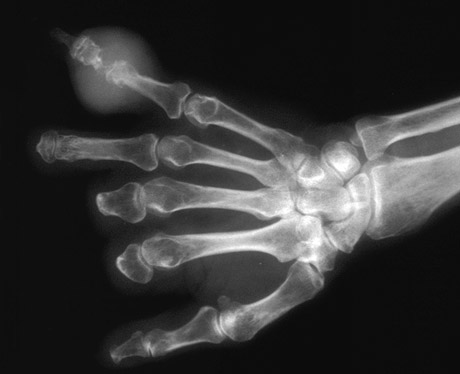

| Here is gouty arthritis involving a hand. Note the tophus with destruction of the bone. Unlike rheumatoid arthritis, the bone at the margins of the destruction is sclerotic with gout. This process has already led to the loss of parts of three digits. |